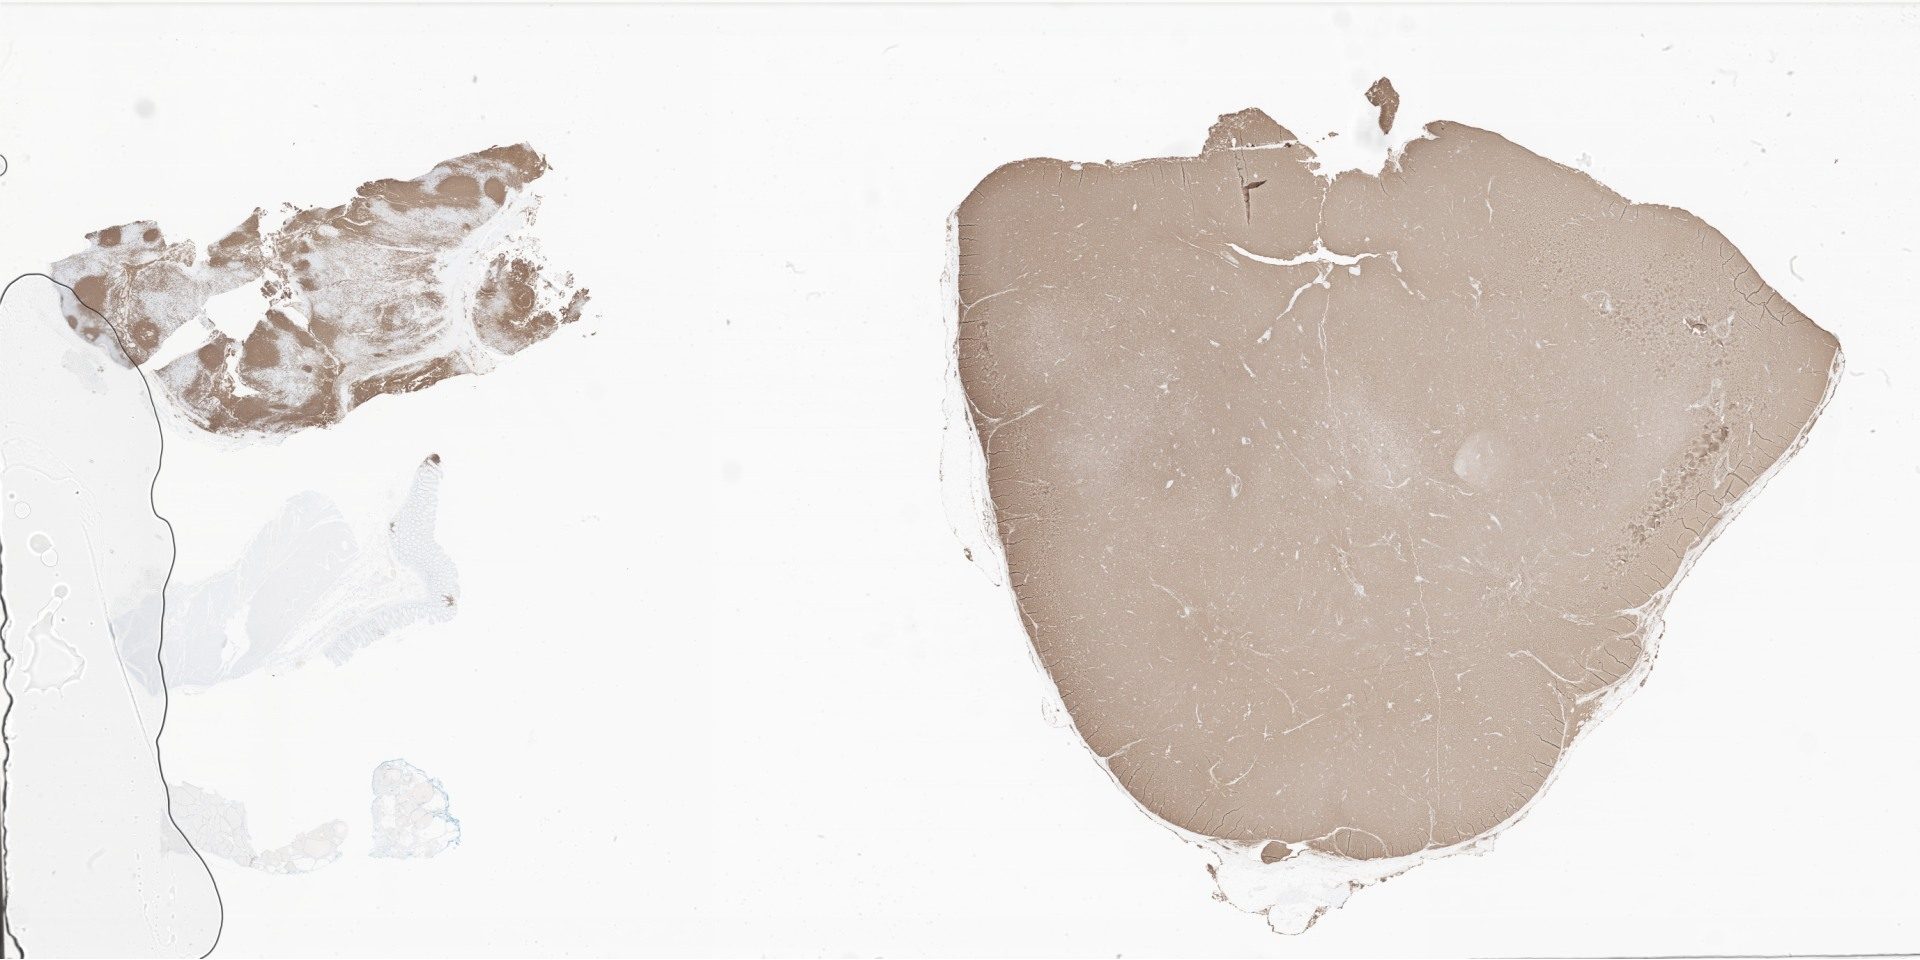

CD20.svs

176345

x

88098

@

40X

Cyclin D1.svs

117181